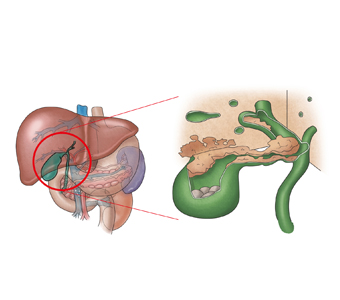

담낭암의 주요 원인은 담석과 용종으로 여겨집니다. 이형성-암 연쇄 과정의 주원인이 만성 염증이며, 이를 유발하는 주요 원인이 담석이라는 점에서 담석은 담낭암의 가장 중요한 위험 인자입니다. 특히 3cm 이상의 담석, 장기간 보유한 담석, 도재 담낭, 담석과 동반된 췌담관 합류 이상, 만성 장티푸스 보균자 등이 위험 인자로 여겨집니다. 또한 신생물성 용종이 담낭암과 관련될 가능성은 5~10% 정도인데, 크기가 1cm 이상인 경우, 50세 이상이면서 무경형 단일 용종인 경우, 담석이 동반된 경우 등이 위험 인자로 꼽힙니다.

담낭 용종, 궤양성 대장염, 원발성 경화성 담관염, 선천성 간 섬유증 등이 있는 분은 반드시 주치의와 상의하여 정기 검진 및 적절한 치료를 받아야 합니다. 담낭 결석 환자 중에서 담낭암이 발견되는 경우는 1% 미만이므로, 담낭 결석이 있다고 해도 증상이 없으면 미리 담낭을 절제할 필요는 없습니다. 담석에 의한 증상이 있는 경우에만 담낭을 선택적으로 제거하면 됩니다.

하지만, 담석이 원인으로 보이는 담낭암 환자의 비율이 낮지 않다는 점과, 1990년대 이후 보편화된 복강경 담낭 절제술이 환자에게 부담이 적은 점 등을 고려할 때 무증상 담석증의 경우에도 수술을 고려할 필요가 있습니다. 췌담관 합류 이상의 기형, 석회화 담낭이 발견되면 담낭암의 발생률이 매우 높기 때문에 이런 때는 담낭을 제거하는 수술을 받아야 합니다.